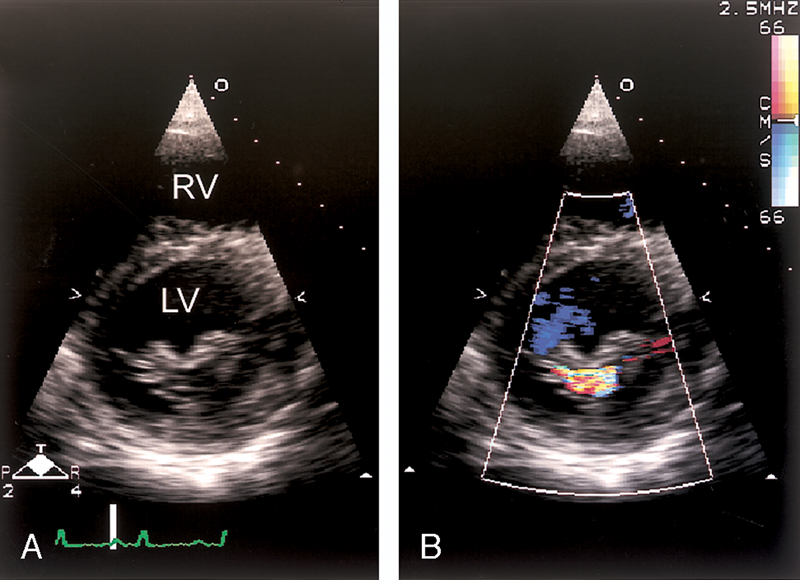

فحوصات تشخيصية لبعض امراض القلب والشرايين التاجية